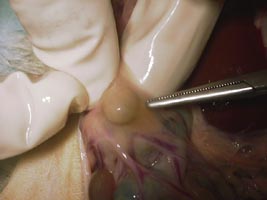

副腎腫瘍と悪性リンパ腫で死亡したフェレットの解剖写真です。貴重な画像です。

| H14.3月 | 死亡 解剖の結果、肺・肝臓・膵臓・副腎に転移。悪性リンパ腫との診断。 |

核小体明瞭な不整形の核と乏しい胞体を有するリンパ球類似の異型細胞が既存の組織を置換するようにびまん性に増殖している。